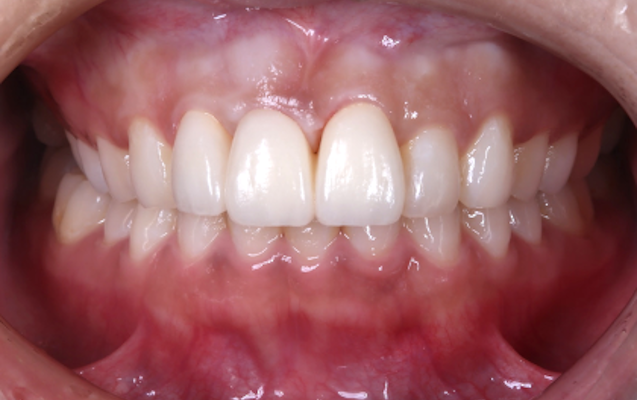

セラミッククラウンはご本人の歯を土台にしながら審美面を大きく改善でき、また噛み合わせや歯並びの矯正なども合わせて対応できることが特徴です。

当院では患者様一人ひとりに向き合った精密検査・診断を通してお口全体のバランスを整え、機能的で長持ちする審美治療としてセラミッククラウンをお作りしています。

(実際の症例)